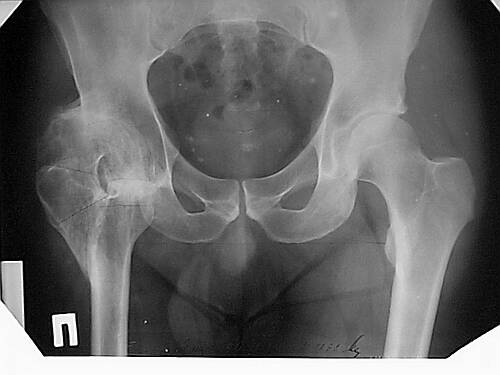

Уважаемые коллеги!Женщина, 35 летВ прошлом по поводу врожденного вывиха бедра перенесла операцию остеотомии по Шанцу

с удлинением правой ноги за счет бедра на уровне диафиза. В последнее время прогрессируют боли в правом тазобедренном суставе, порочное положение правой ноги, затруднена ходьба.Вопросы:1) Целесообразно ли эндопротезирование правого тазобедренного сустава?2) Целесообразный ли следующие действия: канал бедренной кости предполагаем вскрыть для введения ножки протеза на высоте угловой деформации, предполагаем низведение большого вертела с мышцами; протез будет подобран индивидуально, предполагается умеренная версия?В приложении рентгенограммы и трехмерная КТ.В цветном и более качественном варианте КТ размещена здесь

Наше общее мнение - проведение клиновидной остеотомии в зоне дополнительной точки опоры с ее иссечение и укорочением бедра, протезирование ножкой Вагнера.

Похожий случай представляем на ретгенограммах. Операция выполнена в 1996 г.